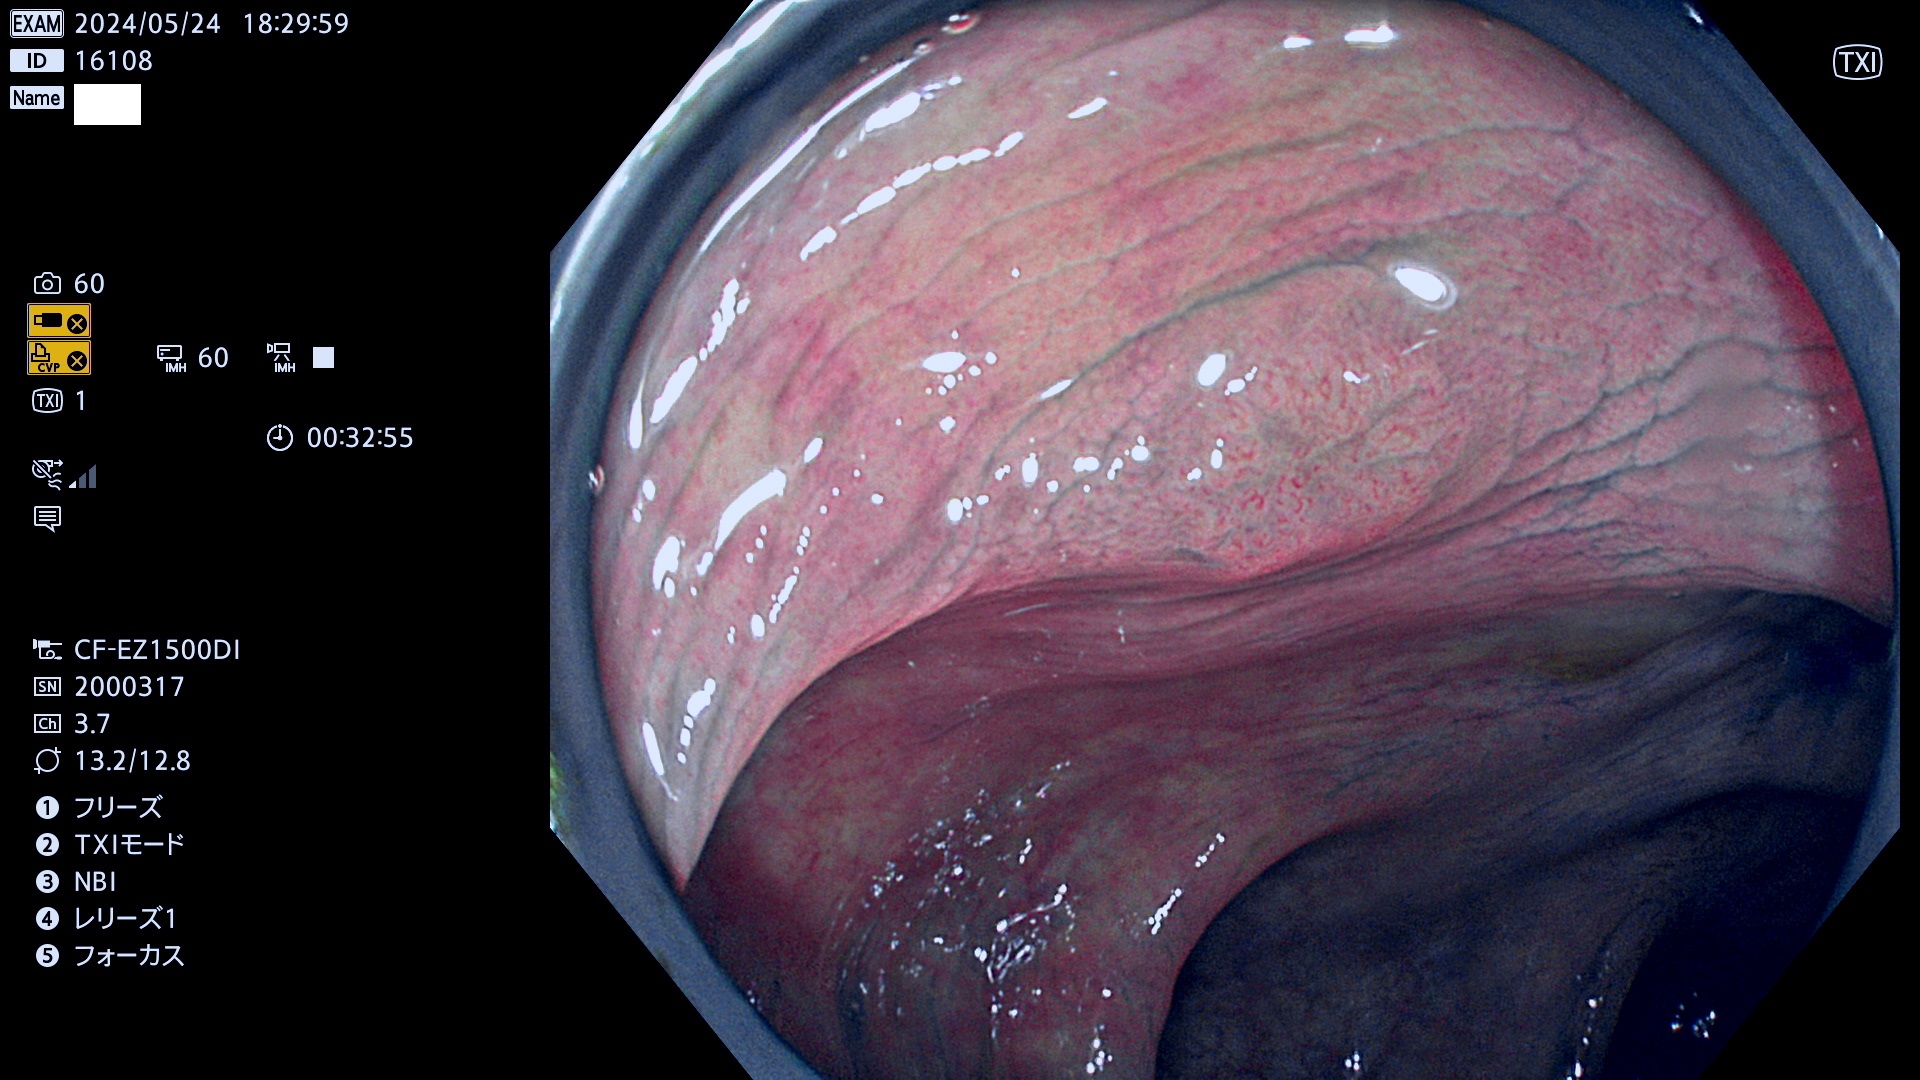

表面型腺腫(Flat Adenoma)の中で、完全に平坦な物をUb、陥凹している物をUcと呼びます。平坦隆起型(Ua)よりも、発見が難しく危険な病変です。

ビランと鑑別の難しい陥凹型腺腫